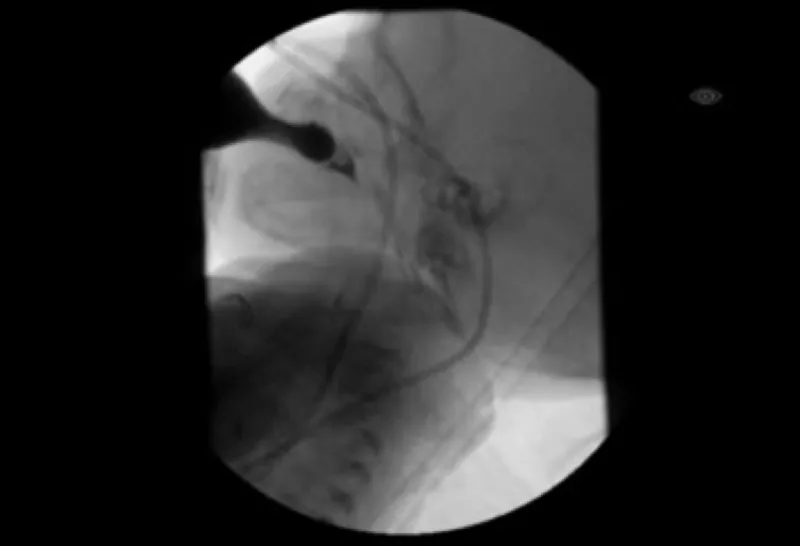

Imaging from modified barium swallow study

Figure 2b. What an MBS looks for

During the MBS, the liquid a child drinks includes a special dye that can be seen on X-ray. We watch as the dye moves from the bottle or cup, though the mouth and throat, and can see if it is entering the child’s airway (aspiration) while he or she feeds. (Photo courtesy of Katie Engstler, SLP)